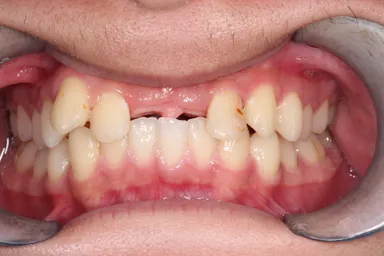

<症例(19歳男性)>

自転車転倒により上の前歯を喪失した患者で入れ歯を入れるも紛失し、インプラント治療以外で治療法がないかと移植に希望をもって当院へ来院されました。当初は下の両側の小臼歯2本を移植し、矯正で抜いた部分を閉鎖しようと検討したものの、矯正医よりスペースの閉鎖は困難と診断され断念。家族、本人の熱意もあり、「埋伏の親知らず」を移植する計画を立て、3D-CTと3Dプリンターを用いての精密なシミュレーションを行った上で施術を行いました。